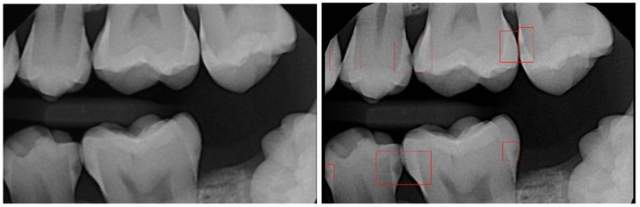

在口腔医疗领域,AI应用最为广泛的也是跟阅片检测相关。拿患病率最高的龋齿来说,传统的诊断依靠X 射线牙片及直接的口内检查,以此发现咬合龋。但对于牙齿根部的龋齿、临间龋和根面龋等潜在龋齿,难以发现,容易漏诊。辅助龋齿检测的AI模型可以代替医生对牙片进行精准的龋齿侦查,这种专项的AI模型对龋齿斑的敏感度高于人类有限的视力。

口腔医疗领域盛产大量的牙科X光检查图像数据,容易匿名化,在开发牙科的AI放射训练系统时非常有价值,方便AI技术的介入。并且对于牙医来说,没有像其他内科、专科医生一样可以配备训练有素的放射科技师,口腔AI的影像分析可以作为媲美人类的准确率较高的助手来使用,成为牙医的第二双火眼金睛。